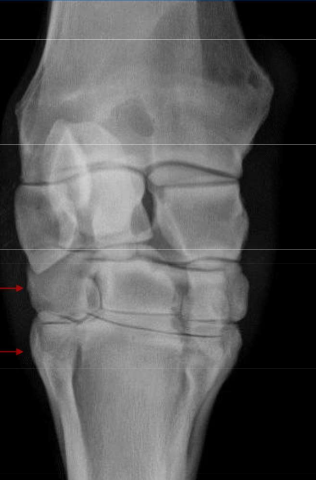

What is this lesion

OCD of the lateral malleolus in horse hock